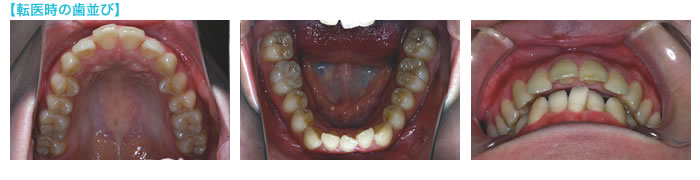

こちらの患者さんは、半年ほど前から別の歯科医院で取りはずしのできる"拡大装置(※)"を用いて、歯を抜かずに歯並びを拡大する矯正治療を行っていたそうです。左は、患者さんが使っていた拡大装置の写真と、転医されてきたときのお口の写真を重ね合わせて作った装着中のイメージ写真です。

上の歯並びは隙間があり、下の歯並びはでこぼこがある状態でした。下の左側の前歯(中切歯)は唇側に出ていたため、約3年前に別の歯科医院で抜歯したとのことでした.そのため下の歯の正中は左側へ約2ミリずれていました。